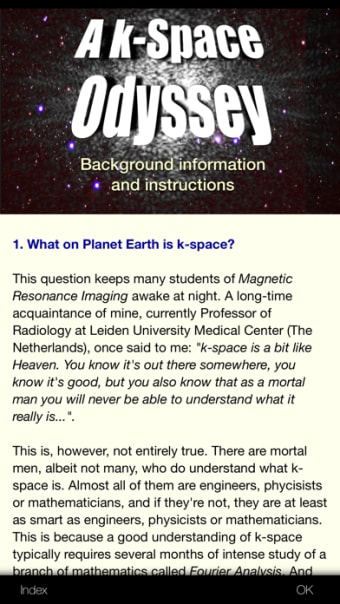

Een volledige versie app voor iPhone, door Eltjo Haselhoff.

A K-Space Odysseyis een app met volledige versie voor iPhone, die deel uitmaakt van de categorie ' Geneeskunde'.

Over A K-Space Odyssey voor iPhone

Een K-Space Odyssey is beschikbaar voor iOS 12.1.2 of hoger. De huidige versie van de software is 1.9.1 en u kunt deze alleen in het Engels krijgen.